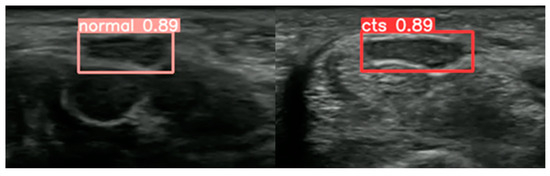

Dynamic Analysis of the Median Nerve in Carpal Tunnel Syndrome from Ultrasound Images Using the YOLOv5 Object Detection Model

- Wu, C.H.; Syu, W.T.; Lin, M.T.; Yeh, C.L.; Boudier-Revéret, M.; Hsiao, M.Y.; Kuo, P.L. Automated Segmentation of Median Nerve in Dynamic Sonography Using Deep Learning: Evaluation of Model Performance. Diagnostics 2021, 11, 1893. [Google Scholar] [CrossRef]

- Shinohara, I.; Inui, A.; Mifune, Y.; Nishimoto, H.; Yamaura, K.; Mukohara, S.; Yoshikawa, T.; Kato, T.; Furukawa, T.; Hoshino, Y.; et al. Using deep learning for ultrasound images to diagnose carpal tunnel syndrome with high accuracy. Ultrasound Med. Biol. 2022, 48, 2052–2059. [Google Scholar] [CrossRef]